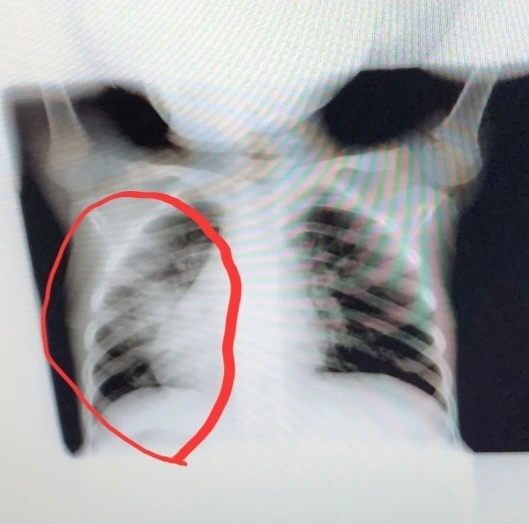

요즘 독감과 폐렴이 유행인데, 얼마 전 소은이는 마이코플라즈마 폐렴, 남편은 A형 독감을 앓았다. 마이코플라즈마폐렴의 가장 큰 특징은 항생제를 복용해도 열이 떨어지지 않는 것. 일반 감기와 달리 마이코플라즈마 폐렴은 열도 높게, 오래 난다. 특히 기침이나 가래가 심하고 발열이나 오한 인후통도 심하다. 소은이도 밤이 되면 40도가 넘게 올랐지만 검사 결과 코로나도 독감도 아니었다. 5일이 지나도 열이 잡히지 않아 소아과에서 엑스레이를 찍고 나서야 폐렴이라는 걸 알게 되었다.

하얗게 보이는 게 폐렴의 흔적